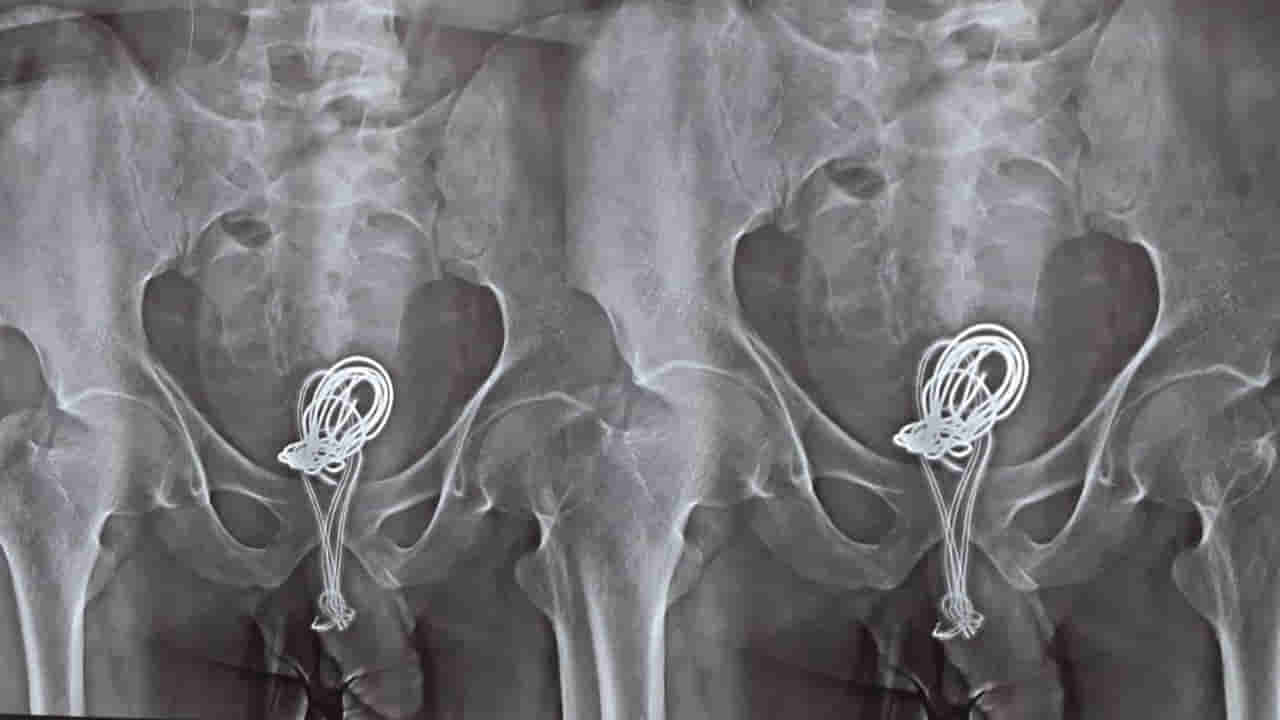

ఇక అతడి బాధను చూసిన కుటుంబసభ్యులు కంగారుపడి.. ఆస్పత్రికి తరలించారు. అక్కడ డాక్టర్లు టెస్టులు చేయగా.. మూత్రాశయంలో చార్జర్ను గుర్తించి ఆశ్చర్యపోయారు. హుటాహుటిన ఆన్ బిన్హ్ ఆసుపత్రి వైద్యులు.. సుమారు రెండు గంటల పాటు శస్త్రచికిత్స నిర్వహించి దాన్ని తొలగించారు. మొదటిగా డాక్టర్లు ఎండోస్కోపిక్ సర్జరీ 30 నిమిషాలు కొనసాగించగా.. ఆ వైర్ శరీరంలో లూప్లుగా చుట్టుకుని ఉండటంతో.. ఆ ప్రక్రియ క్లిష్టం అయింది. అంతేకాకుండా మూత్రాశయంలోని కొంత భాగం దాని వల్ల కుళ్లిపోవడాన్ని డాక్టర్లు గుర్తించారు. అయితేనేం చివరికి ఆపరేషన్ చేసి దాన్ని బయటకు తీశారు. రెండు రోజుల అనంతరం సదరు బాలుడికి కౌన్సిలింగ్ ఇప్పించి పంపించారు.